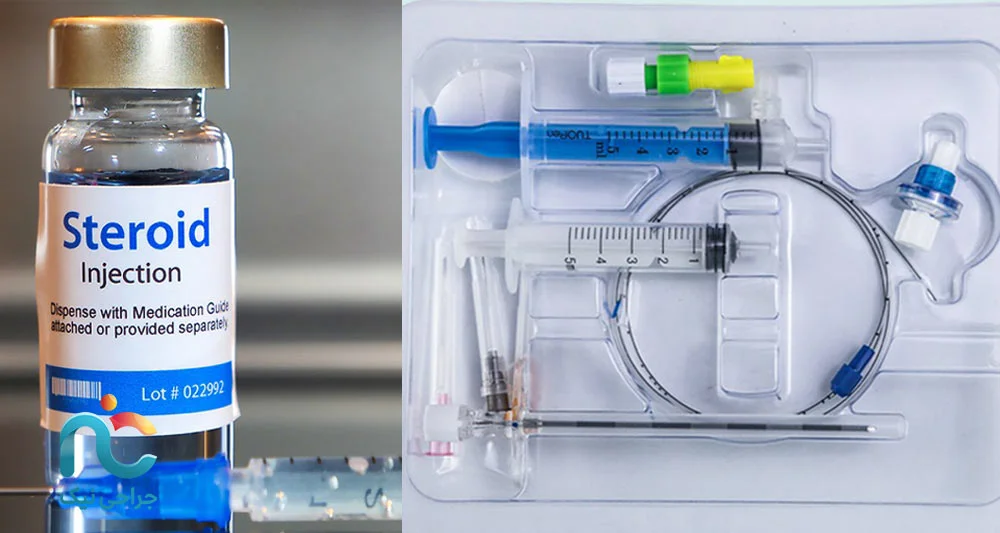

شاید برایتان سوال باشد که «در این تزریق، دقیقا چه چیزی وارد بدن من میشود؟». ترکیب دارویی، بر اساس شرایط هر بیمار و تصمیم پزشک تعیین میشود، اما به طور کلی شامل سه جزء اصلی است. یک بخش داروی ضدالتهاب قوی است که از خانوادهی کورتونهاست و با دوز کنترلشده استفاده میشود. این دارو مستقیما در کنار اعصاب ملتهب قرار میگیرد و کمک میکند ورم و التهاب اطراف عصب کم شود و در نتیجه فشار روی عصب کاهش پیدا کند.

بخش دیگر، داروی بیحسی موضعی است؛ شبیه همان چیزی که برای بیحسی دندان استفاده میشود، اما اینبار اطراف ریشههای عصبی کمر تزریق میشود تا هم در ساعات اولیه بعد از تزریق درد کمتر شود و هم برای ما نشانهای باشد که دارو در محل درست قرار گرفته است؛ چون بیمار معمولا احساس سبکتر شدن یا کاهش درد در همان مسیری که قبلا درد داشته، توصیف میکند.

گاهی در کنار این دو، از مقدار مشخصی محلول نمکی (سرم) هم استفاده میکنیم تا داروها در فضای اپیدورال بهتر پخش شوند و اگر چسبندگیهای بافتی وجود دارد، تا حدی از هم باز شوند. همهی اینها با هم، با هدف کاهش التهاب، کاهش درد و بهبود توان حرکت شما تزریق میشوند.

عامل مهم بعدی، خودِ نوع تزریق و داروهای استفادهشده است. در تزریق اپیدورال کودال معمولاً از ترکیبی از داروهای ضدالتهاب (استروئید) و بیحسی موضعی استفاده میشود. نوع و برند دارو، دوز مصرفی، و اینکه آیا برای شما نیاز به تزریقهای تکراری (مثلاً یک سری ۲ یا ۳ تزریقی در چند هفته) در نظر گرفته شود یا یک تزریق تک، روی هزینه نهایی تأثیر میگذارد. بعضی بیماران با یک تزریق پاسخ خوبی میگیرند، اما در برخی موارد بر اساس شواهد علمی و تجربه، سری چندجلسهای توصیه میشود که طبیعتاً هزینه مجموع را تغییر میدهد.